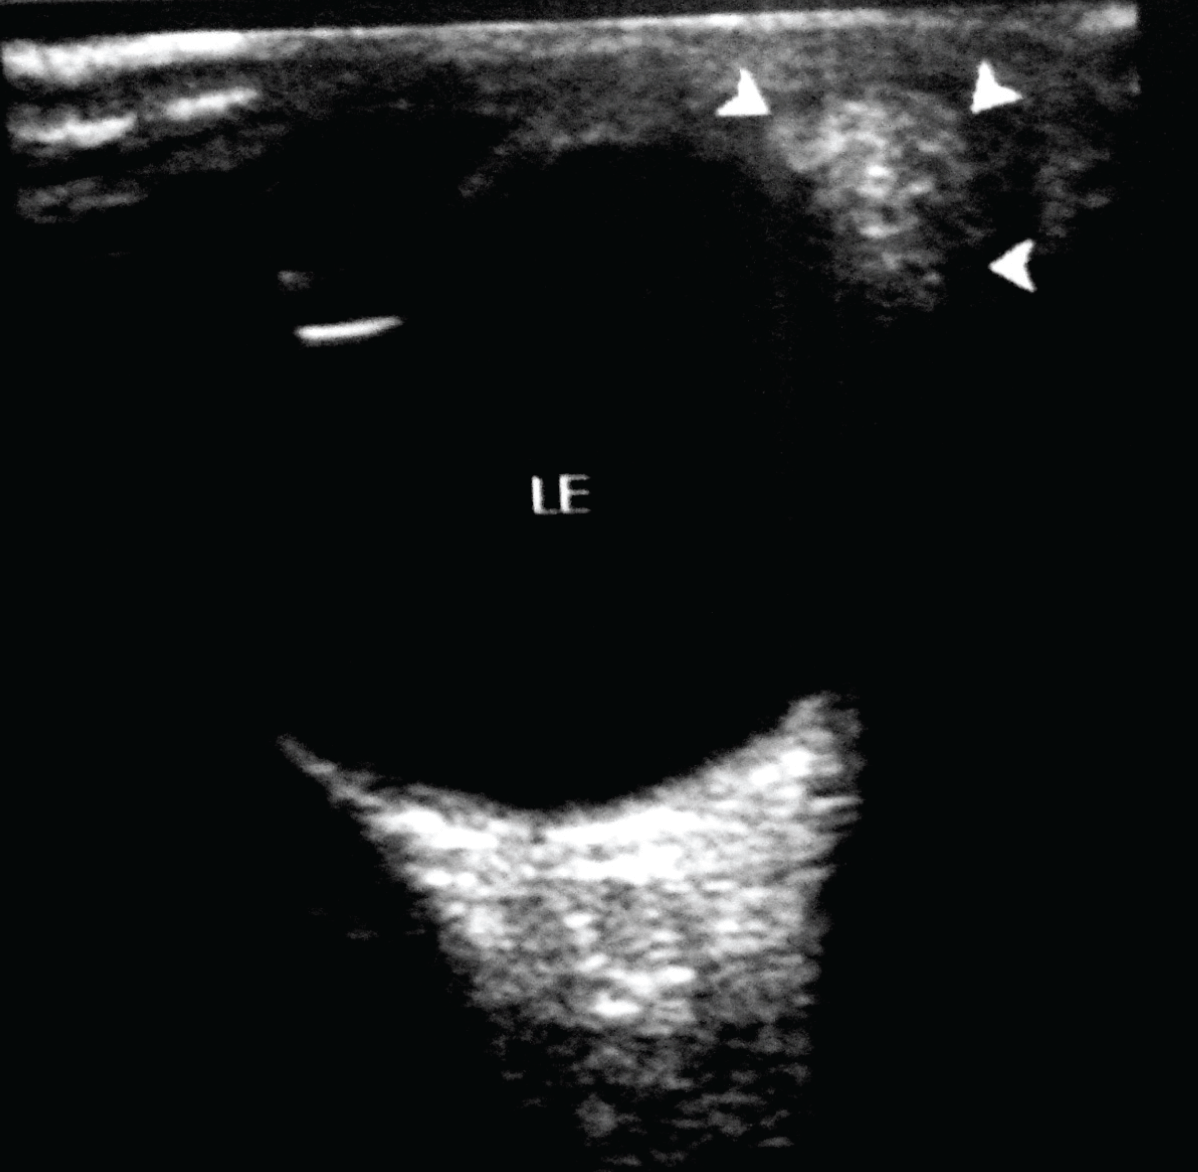

A 12-year-old Asian girl presented to our department for computed tomography (CT) scan of orbits for evaluation of ocular dermoid cyst. The child was born to non-consanguineous parents with uneventful prenatal and antenatal period. There was no relevant family history. Her mental status was normal and there was no evidence of developmental delay. Left limbal dermoid cyst measuring 0.5x0.5 cm with hair follicles was seen at 5 o’clock position since birth, (Figure 1A-B) which is painless and not increasing in size. A dermal tag was seen at the lateral canthus of the left upper eyelid. (Figure 1A) There was no redness or discharge from the eyes and ocular motility was normal bilaterally. Her visual acuity was normal (6/6). An accessory preauricular tag was seen on the left side. (Figure 1C) Audiological examination shows no evidence of hearing impairment. Intraoral examination revealed malocclusion of lower dentition. (Figure 2) Cardiovascular system and central nervous system were normal. Hematological investigation showed hemoglobin 11.9 g/dL, total leukocyte count (TLC) 8500/μL, neutrophils 38%, lymphocytes 48%, eosinophils 15%, monocytes 5% and platelet counts 274x103/μL. Routine and microscopic urine investigation were within the normal limits. No abnormality was seen on plain radiograph (antero-posterior and lateral views) of cervical and thoracic spine. The CT scan of orbits showed a hypodense lesion of fat attenuation measuring 0.8x0.5 cm on the lateral aspect of the left orbit abutting the lateral margin of the globe, suggestive of dermoid cyst. (Figure 3) Another small similar lesion measuring 0.5x0.5 cm seen at the left limbal region (suggestive of dermoid cyst). Grayscale ultrasonography (USG) of left orbit showed a small echogenic lesion at the limbus. (Figure 4) Clinical and radiological features were suggestive of Goldenhar syndrome. Pediatric consultation was also done to rule out any systemic associations. She was referred to dentist for needful correction of the maloccluded teeth. Surgical excision of the dermoid cysts was done. Postoperative period was uneventful. | ||||||